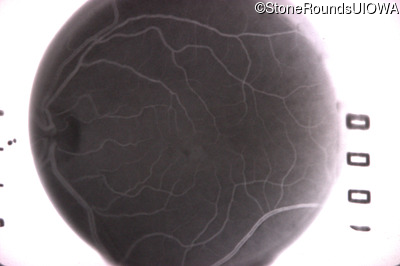

Fluorescein Angiography - Left - 20/20 -1 sc

Exemplar